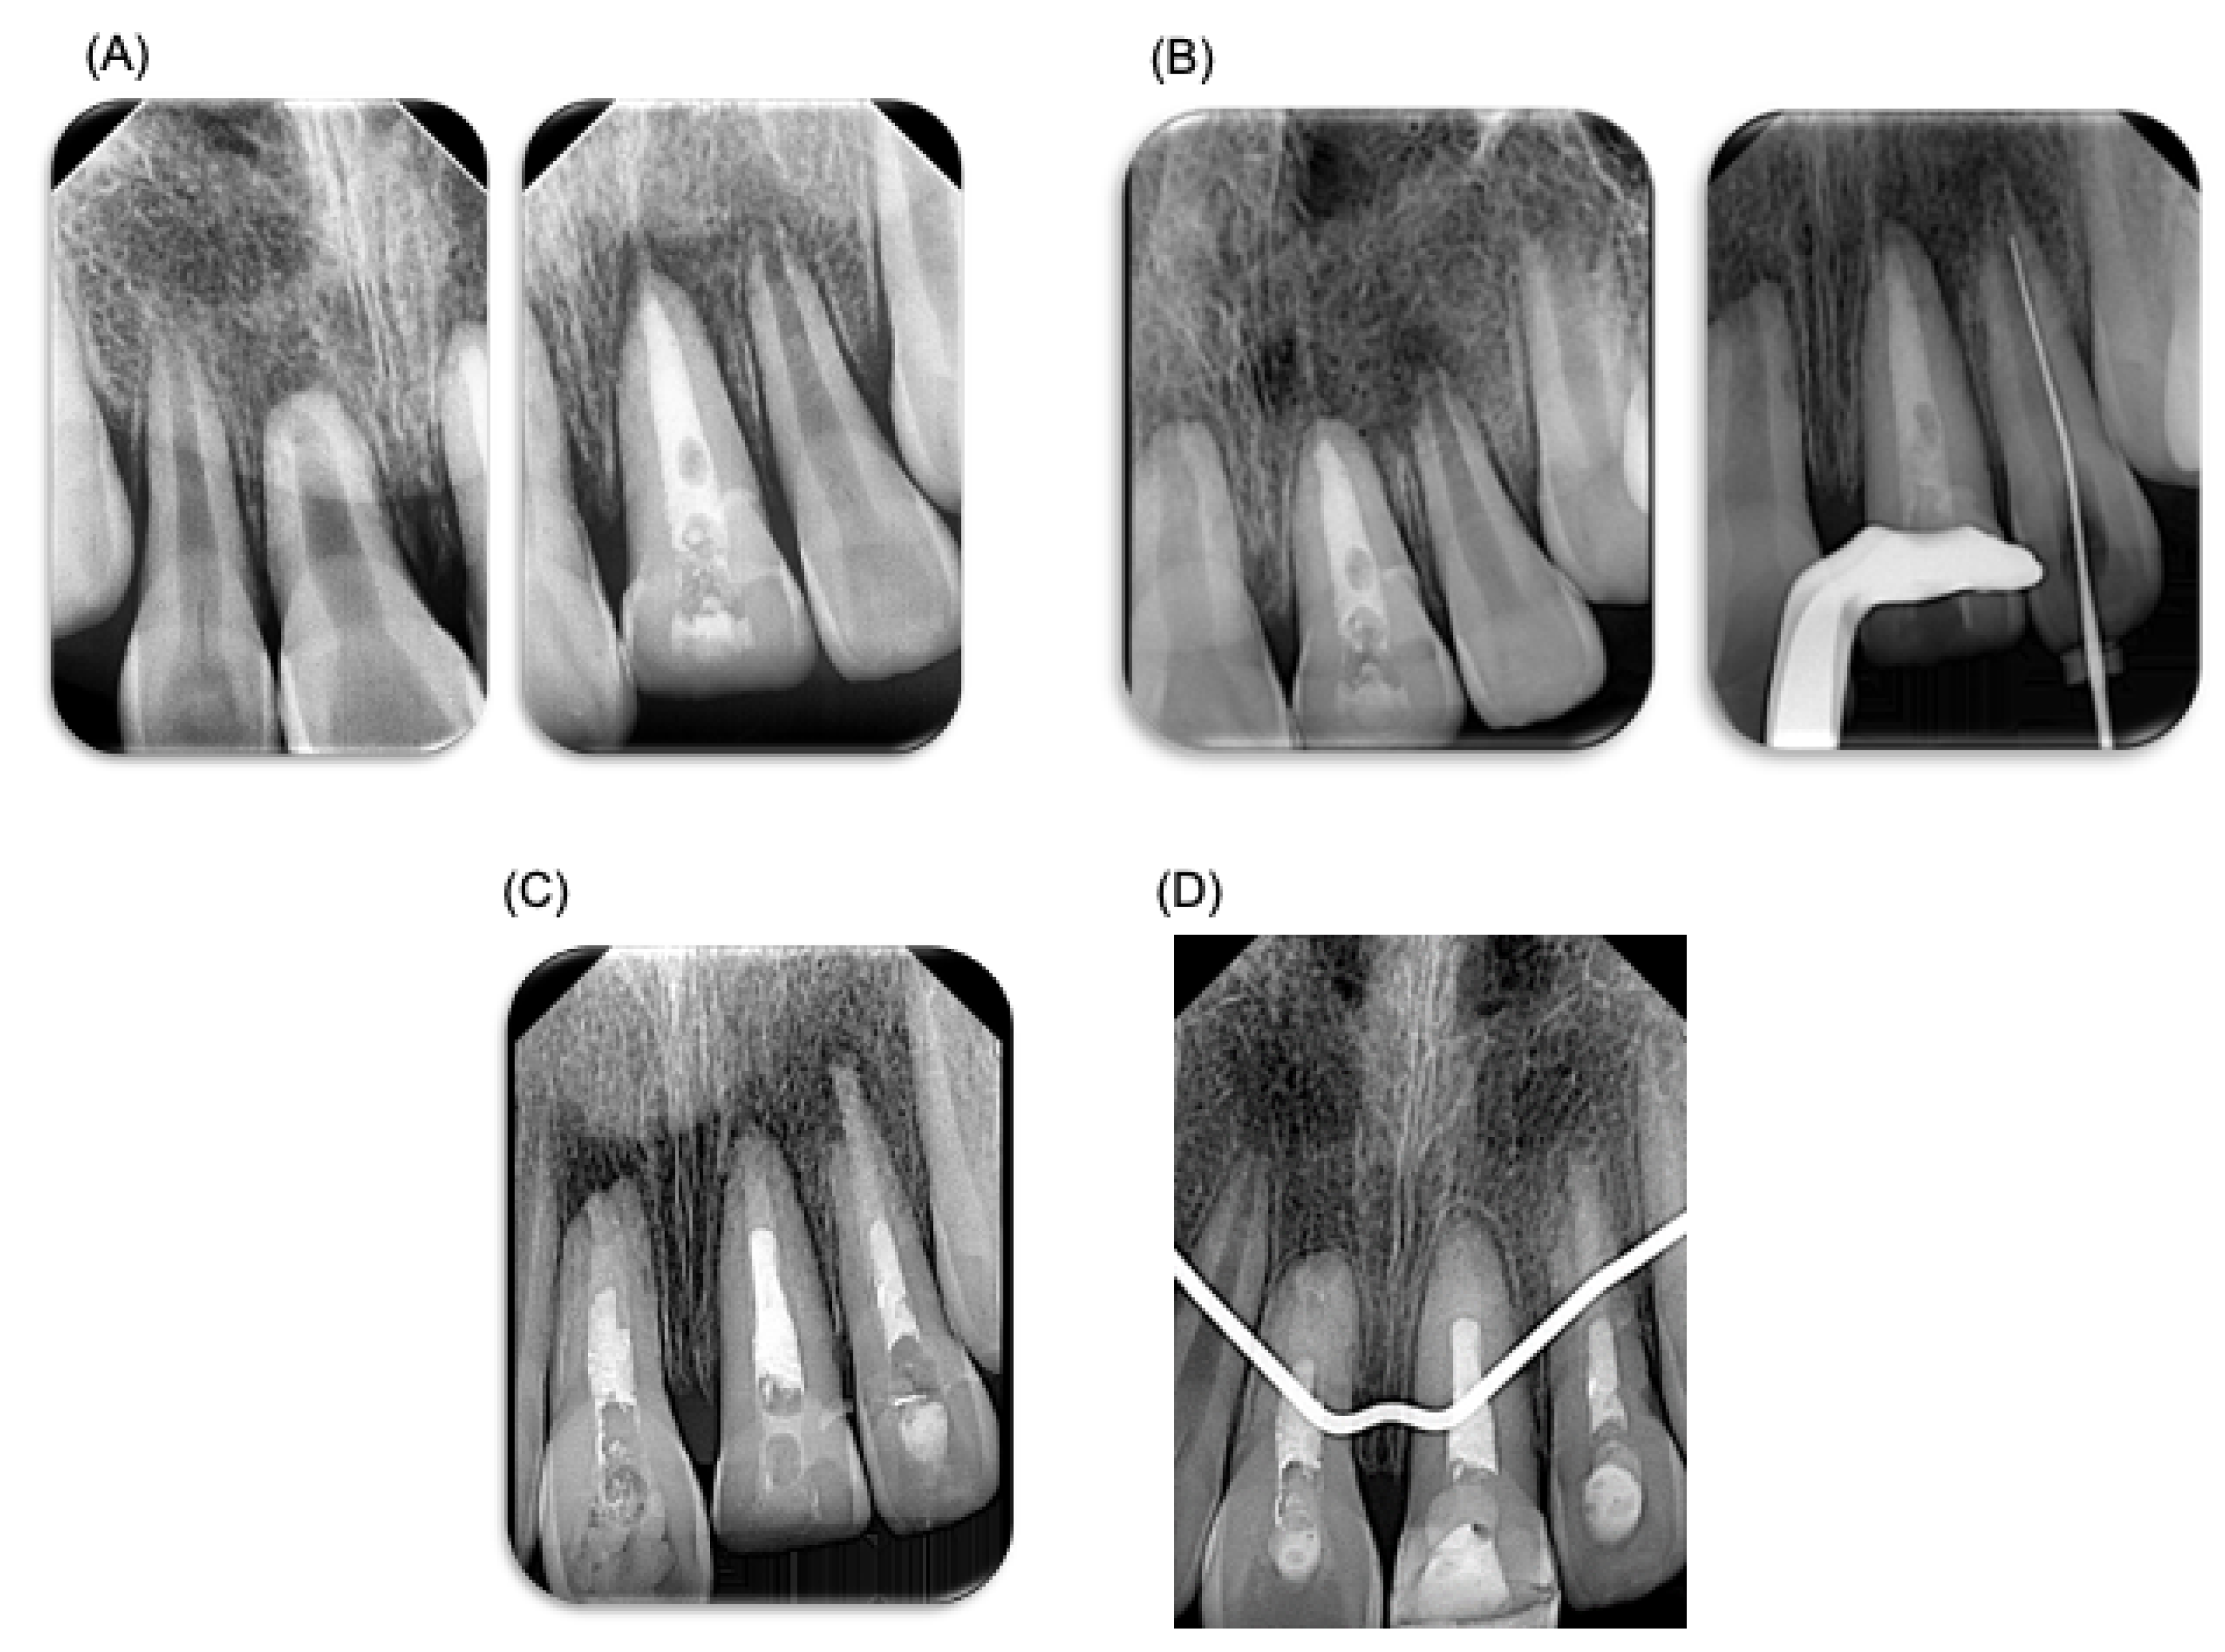

A week later, the patient visited the endodontist for evaluation and diagnostic tests, revealing pulp necrosis in tooth 21. Root canal treatment was performed under local anesthesia using mepivacaine 2% with epinephrine 1:100,000 of anterior dental and nasopalatine nerves (Zeyco, Zapopan, Jalisco, Mexico). Absolute isolation was achieved for the access cavity, and odontometry was performed with a K25 file to 19 mm. Protaper Gold rotary systems and K-Files up to a size 90 file were used. The irrigation protocol included 2.25% NaOCl, followed by final irrigation with sonic activation using NaOCl, saline solution, and 17% EDTA (by using three rechanges during 20 s each solution). Root canals were dried with sterile paper points. Intracanal calcium hydroxide medication mixed with water basis was placed, and a temporary restoration with ProRoot (Cavit, 3M ESPE, Seefeld, Germany) was applied (Figure 3). Three weeks after endodontic treatment, tooth 21 was asymptomatic. However, tooth 22 exhibited grade 3 mobility despite being negative on palpation and percussion. In addition, radiographic examination revealed external root resorption in the apical third of tooth 22; therefore, endodontic treatment was performed on tooth 22, carried out following the same specifications. Three weeks later, the temporary filling in tooth 21 was removed (Figure 3). Root canal treatment was also carried out on tooth 11, and endodontic treatment was carried out following the same specifications. Because the teeth had open apices, a biodentineTM (Septodont, Saint-Maur-des-Fossés Cedex, Paris, France) plug was placed for apical sealing.

Figure 3.

Endodontic treatment. Endodontic treatment performed on patient. (A) X-ray prior to endodontic treatment performed. (B) Control X-ray, 3 weeks after endodontic treatment, where root resorption can be observed. (C) X-ray after the performed endodontic treatment. (D) X-ray at 3 months, where the apical closure of teeth can be observed (teeth 11 and 21). A BiodentineTM plug was placed. This material has a different radio-opacity than gutta-percha material; therefore, in the X-ray it may look like the endodontic treatment was not performed fully.